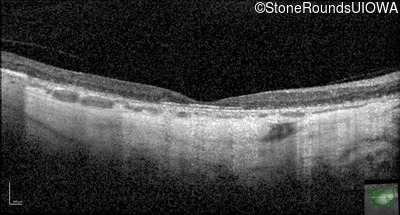

Optical Coherence Tomography - Left - 10/200

Exemplar / OCT Stack